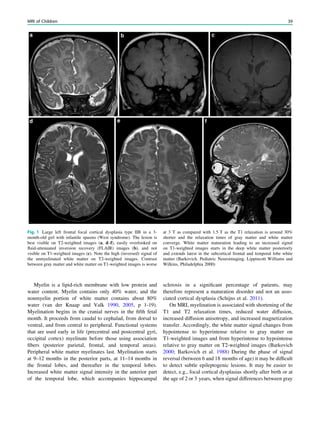

Fig. 1 An 8-year old girl presented with two focal motor seizures and

postictal left arm paralysis. MRI shows superior sagittal sinus

thrombosis (a–c, arrows) with two small hemorrhages at the gray

matter–white matter junction in the right frontal lobe (a, hollow

arrows)

26 H. Urbach